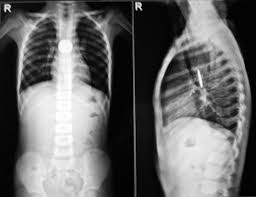

🩻 Difficulty 2 in swallowing – Suspected Esophageal Stricture

Difficulty 2 in swallowing – Suspected Esophageal Stricture

Case Images